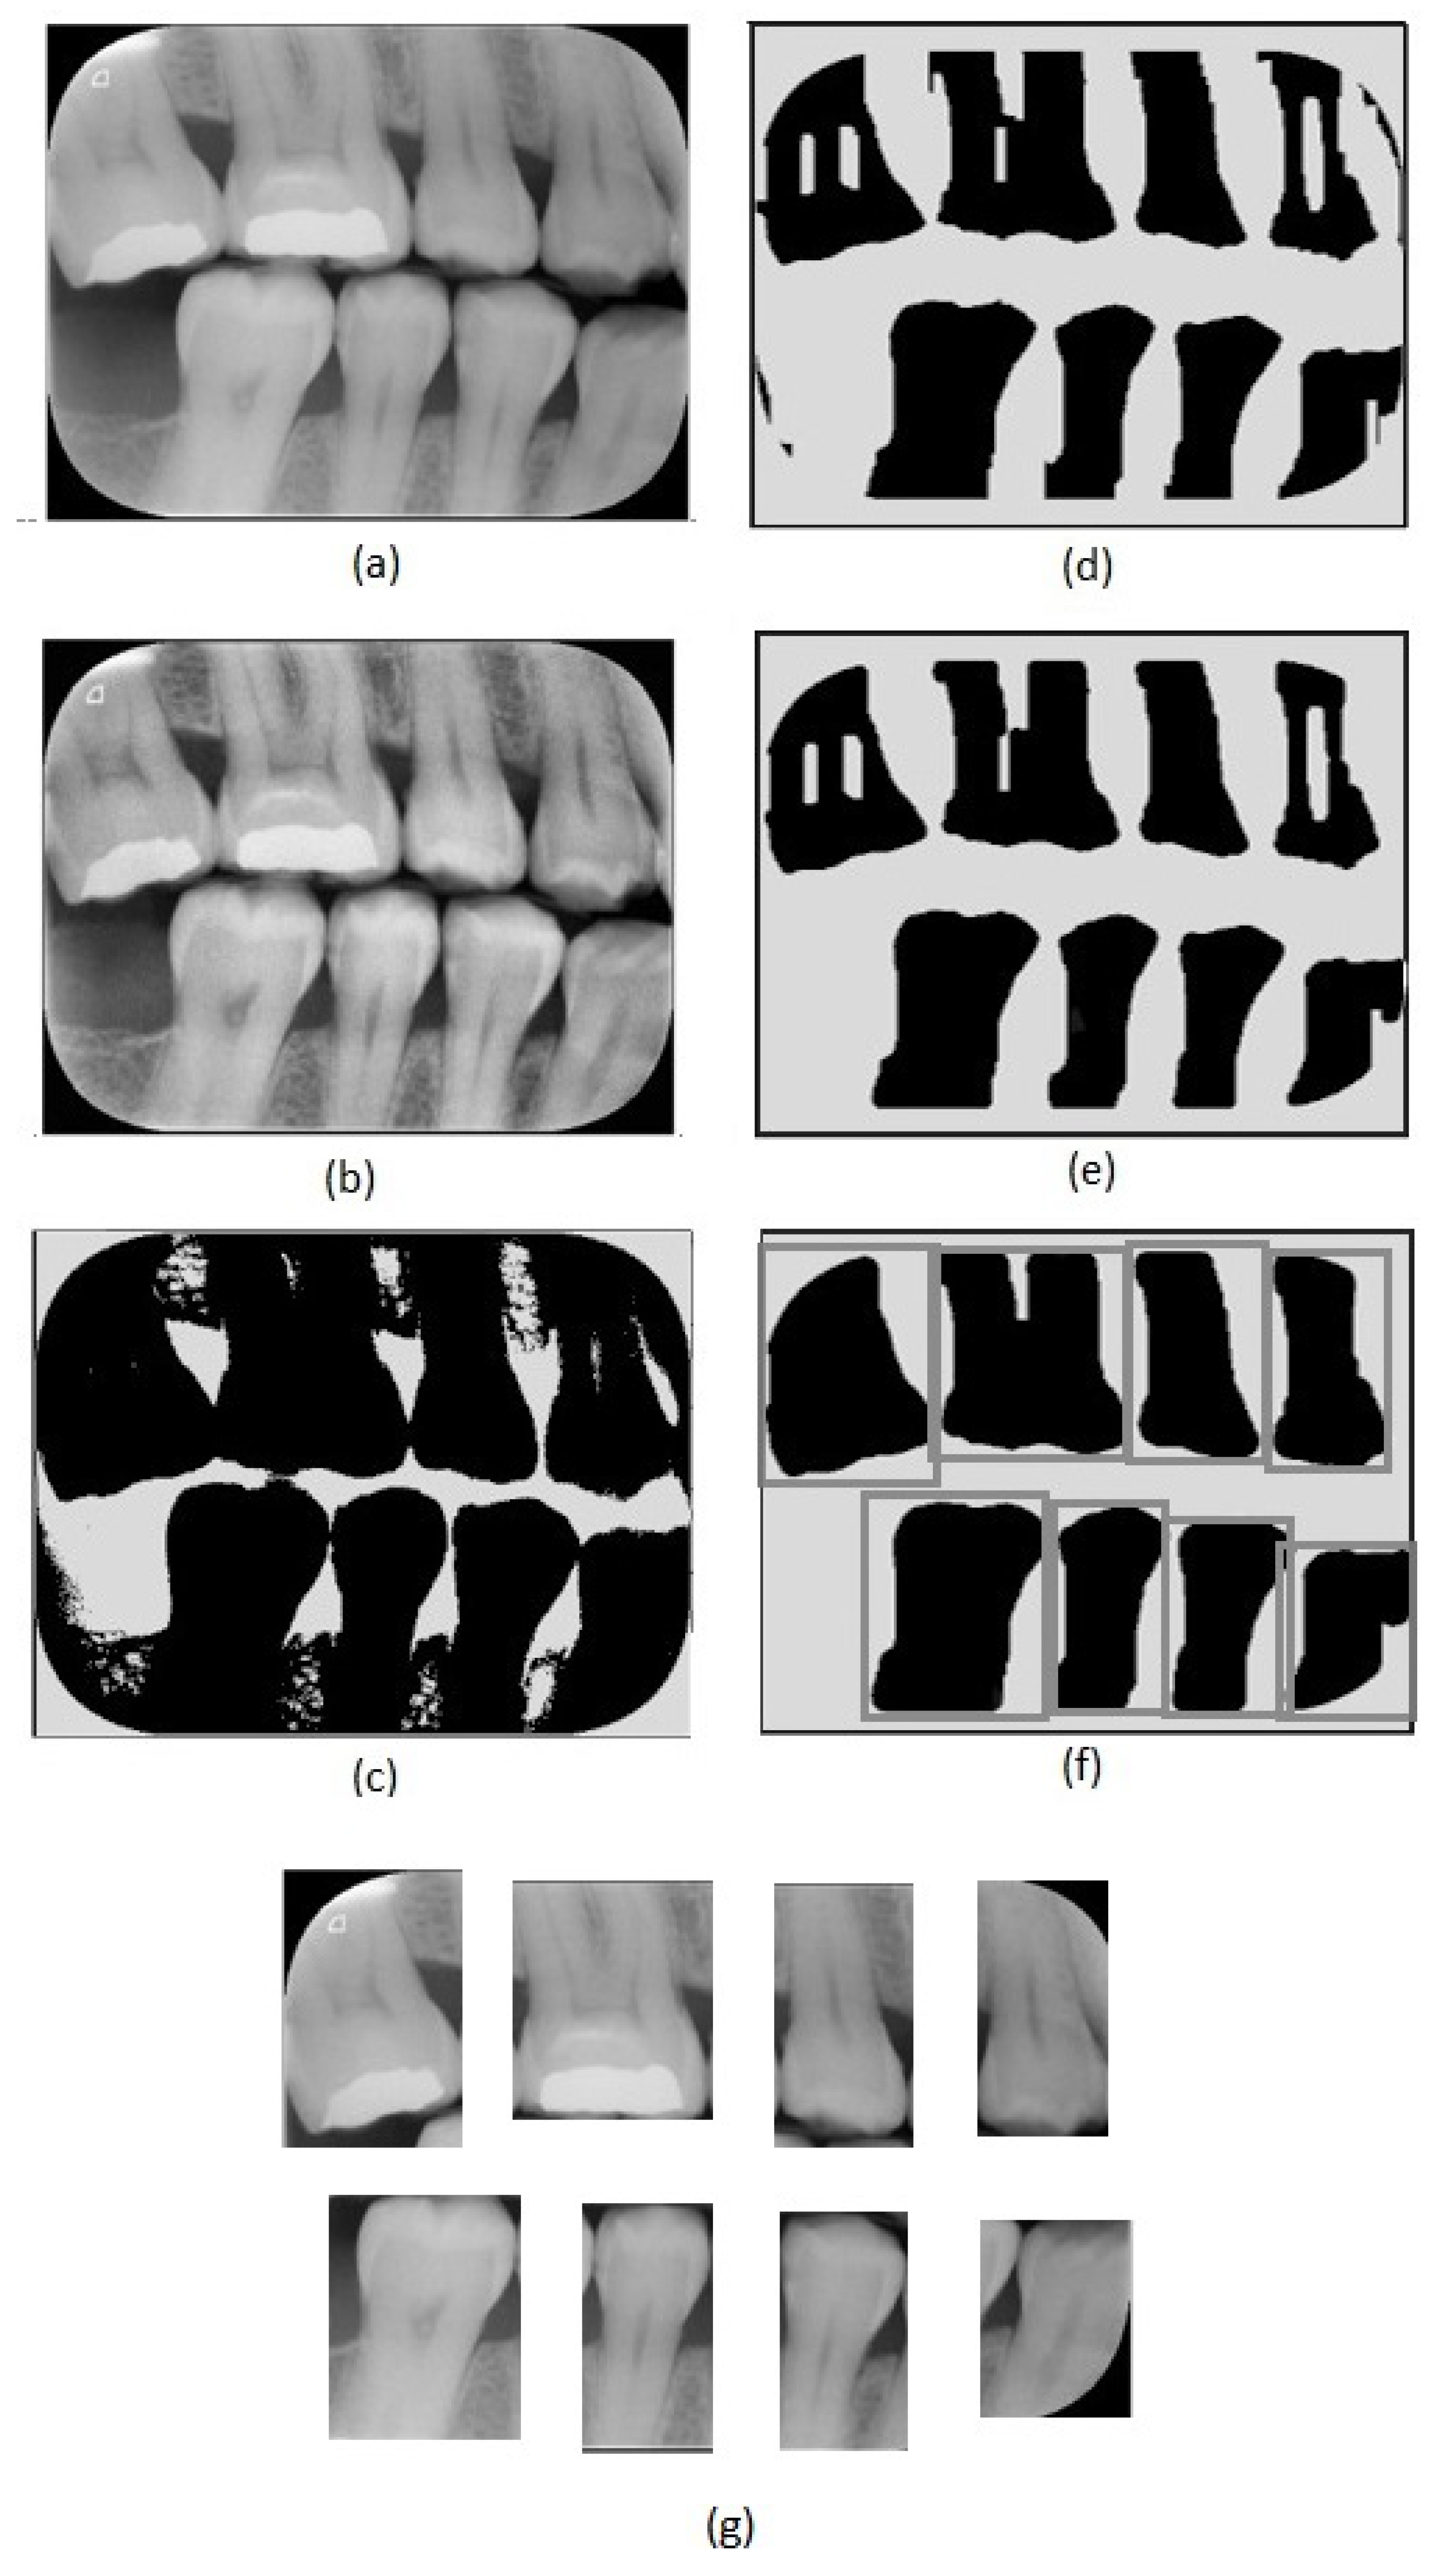

Figure 1.

(a) Representation of an incipient caries lesion, (b) bitewing image with incipient lesion highlighted, (c) representation of an advanced caries lesion, (d) bitewing image with advanced lesion highlighted.

In this work, we consider three different caries stages based on their lesion severity: normal, incipient, and advanced. The normal class consists of teeth with no lesion. The incipient class denotes teeth with superficial lesions affecting the enamel—Figure 1a,b. Finally, the advanced class refers to teeth with advanced lesions, affecting a considerable part of the tooth, expanding into the dentin and the pulp—Figure 1c,d.